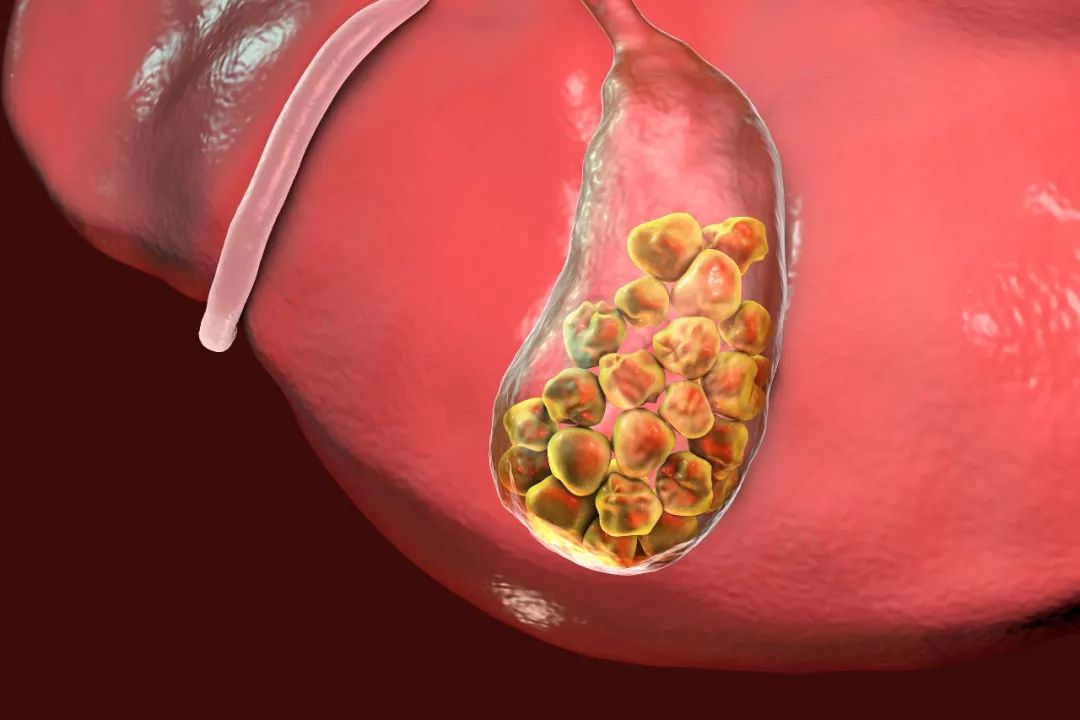

胆结石分好多种,平时大家常说的“胆结石”是指胆囊结石,即胆囊内的结石所引起的疾病。

在中国,胆囊结石的发病率大约为10%左右,也就是每10个人中大约就有1个人患有结石。

为什么会形成胆结石?胆囊结石的成因非常复杂,各种原因引起的胆汁成分变化都可能引发结石。

目前已知与胆结石形成相关的因素包括: